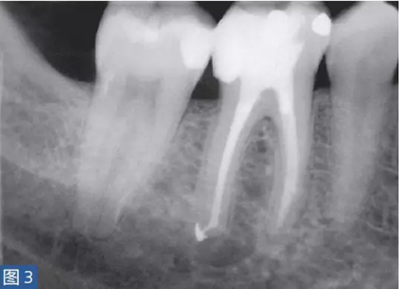

圖3: 46 牙齒SAP。根管治療6個(gè)月后。